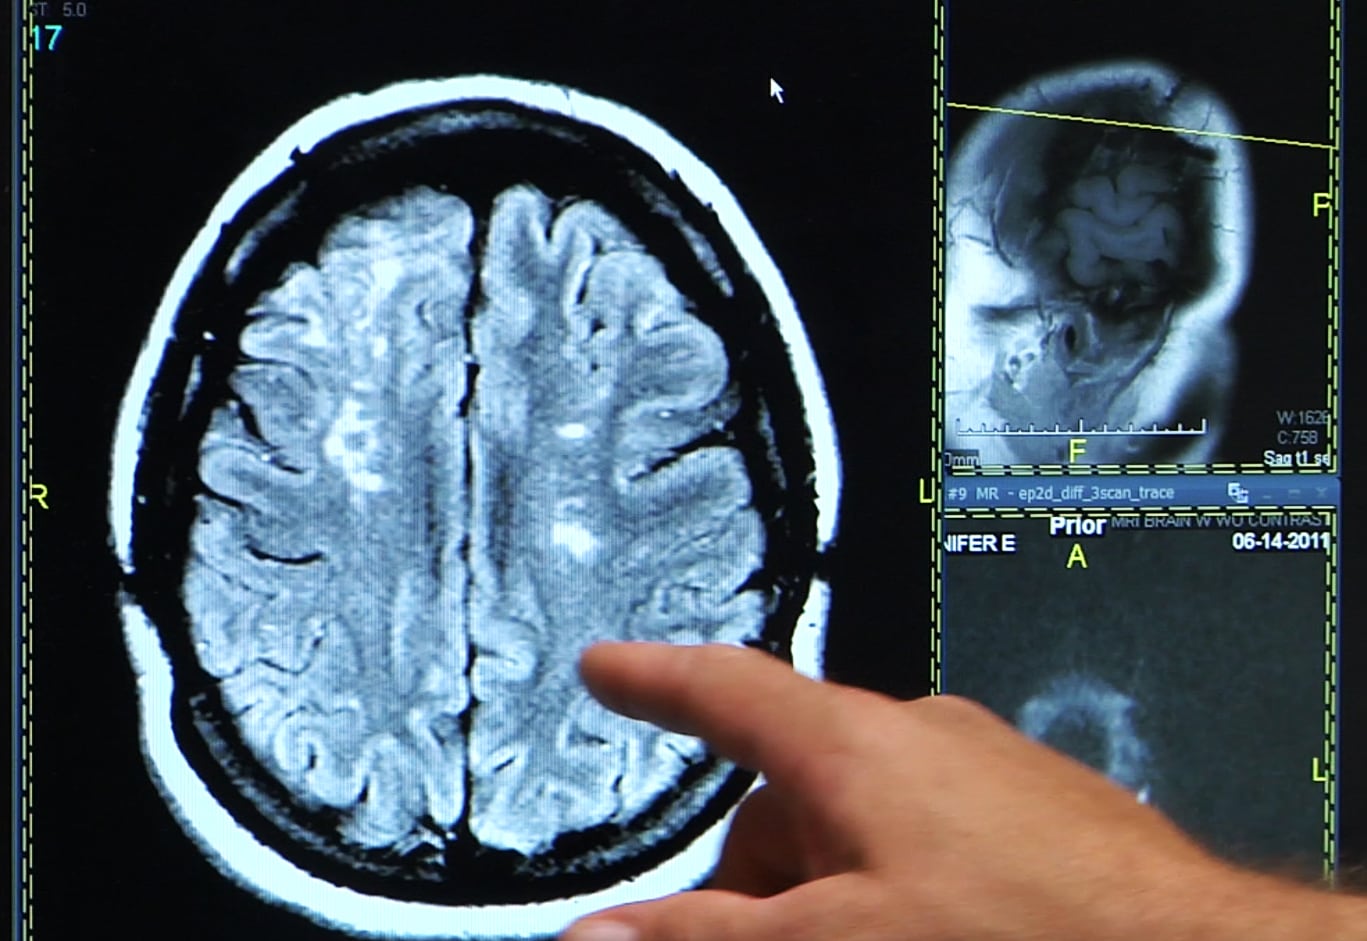

El derrame cerebral ocurre cuando el flujo sanguíneo de una parte del cerebro se interrumpe, causando daño potencial y, en muchos casos, permanente si no se atiende pronto.

“Nuestro cerebro posee áreas especializadas en acciones y controles de movimientos, de los sentidos, del lenguaje, etcétera. Y un accidente cerebrovascular puede generar diferentes síntomas en el cuerpo, que se harán sentir según donde anatómicamente ocurra la lesión cerebral”, explicó Alejandro Andersson, doctor y director del Instituto de Neurología en Argentina.